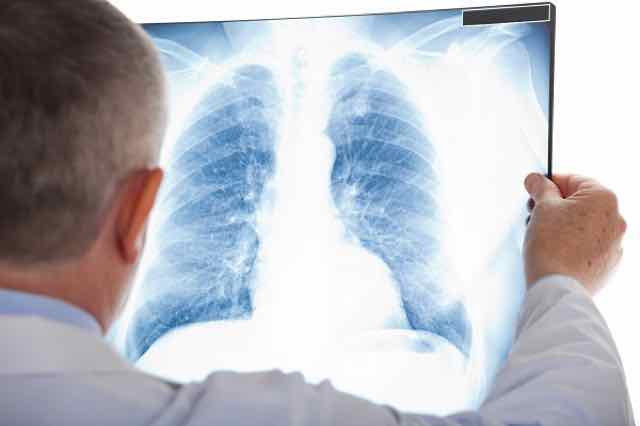

Raio X Do Torax Detecta Covid

Using Lung X Rays To Diagnose Covid 19 Imaging Technology News

Coronavirus X Rays Show Terrifying Damage In Lungs Of Covid 19 Victims World News Mirror Online

Covid 19 Coronavirus Diagnosis Chest X Ray And Ct Scan